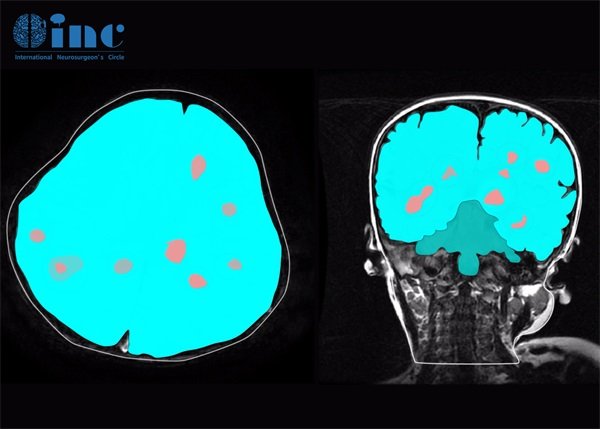

影像学检查是脑海绵状血管瘤确诊的重要工具。目前,磁共振成像(MRI)被广泛应用于此类疾病的诊断。MRI能够清晰地展示血管结构和周围脑组织的状况,能够有效识别血管瘤的大小、形状及其对周围组织的影响。另一个常见的检查方式是计算机断层扫描(CT),它同样能提供有价值的信息,但对某些小的血管改变可能不如MRI敏感。